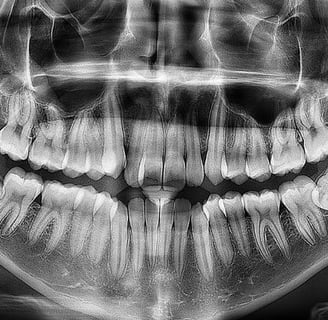

Diagnostic amplu: Aceste radiografii sunt utile pentru diagnosticarea unui spectru larg de afecțiuni dentare și osoase, cum ar fi cariile, infecțiile, fracturile osoase, chisturile sau tumori.

Planificarea tratamentului: Radiografiile panoramice sunt folosite în planificarea tratamentelor stomatologice, precum extracțiile de dinți, intervențiile chirurgicale și tratamentele ortodontice.

Evaluarea dezvoltării dentare: Radiografiile panoramice sunt utile pentru evaluarea dezvoltării dentare, mai ales în cazul copiilor și adolescenților.

Diagnosticul cariilor dentare: Radiografiile panoramice pot evidenția cariile dentare și le pot arăta pe toate dinții.

Evaluarea dezvoltării dentare: Imaginile panoramice sunt utile pentru evaluarea dezvoltării dinților și pentru depistarea oricăror anomalii.

Planificarea intervențiilor chirurgicale: Radiografiile panoramice sunt utilizate pentru planificarea intervențiilor chirurgicale, cum ar fi extracțiile de dinți sau corecțiile ortognate.

Evaluarea afecțiunilor osoase: Aceste radiografii pot ajuta la diagnosticarea problemelor osoase, cum ar fi fracturile sau tumori.

Planificarea tratamentelor ortodontice: Radiografiile panoramice sunt folosite în planificarea tratamentelor ortodontice pentru a evalua poziția dinților și a oaselor maxilare.

Monitorizarea evoluției bolii parodontale: Imaginile panoramice pot fi folosite pentru a monitoriza evoluția bolii parodontale în timp.

Radiografiile panoramice dentare reprezintă o tehnică esențială de imagistică în stomatologie. Acestea oferă o vedere completă a cavității bucale și sunt utile în diagnosticul și planificarea tratamentului pentru o gamă largă de afecțiuni dentare și osoase. Cu beneficiile lor semnificative, radiografiile panoramice rămân o resursă valoroasă pentru profesioniștii din domeniul stomatologiei în îngrijirea dentară modernă.